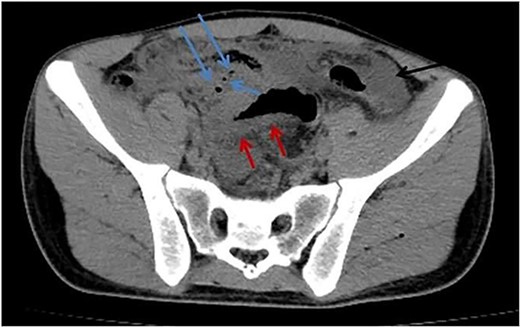

A computed tomography scan without contrast (due to elevated s.creatinine of 2.18) revealed a moderate to severe amount of free fluid in the abdominal and pelvic cavities. The appendix was perforated. The juojenal bowel loops and the rectum showed circumferential wall thickening mostly due to inflammatory process (Figs 1 and 2).

Axial abdomen CT scan without contrast shows pneumoperitoneum (blue arrows), free fluid (black arrow), and sigmoid wall thickening (red arrow).